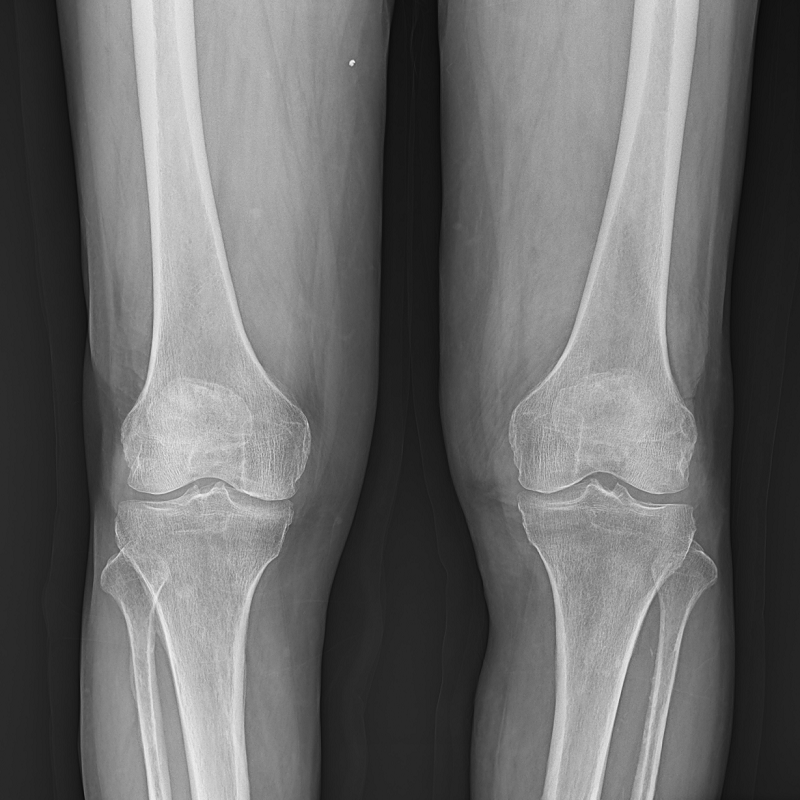

● 圖像拼接

系統(tǒng)可以識(shí)別曝光圖像,無需設(shè)置識(shí)別點(diǎn)即完成精準(zhǔn)拼接,呈現(xiàn)大范圍完整影像。